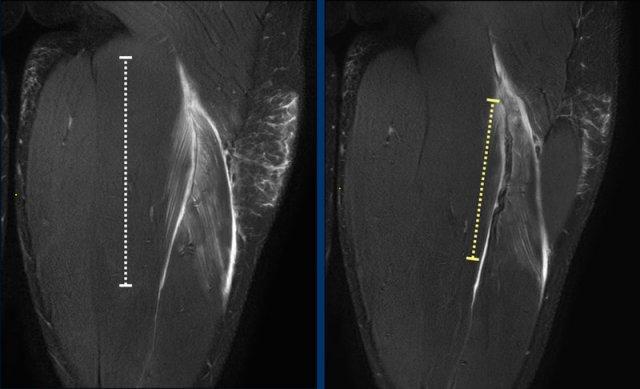

Chiều dài vùng phù nề

Sự hiện diện của phù nề có thể được sử dụng để xác định vị trí tổn thương.

Phù nề thường biểu hiện dưới dạng tăng tín hiệu hình lông vũ bao quanh gân trong cơ và các bó cơ.

Tổng chiều dài vùng phù nề được ghi nhận (đường chấm trắng). Hãy quan sát kỹ hơn phần gân (đường chấm vàng) và tiếp tục đọc.

Chiều dài đoạn gân biến dạng

Khi gân có hình thái bình thường, khả năng căng giãn ở mức độ thấp.

Gân dày lên, gân có dạng gợn sóng, tăng tín hiệu trong gân đều có thể là dấu hiệu của căng giãn mức độ cao hơn.

Trường hợp 1: gân bình thường.

Trường hợp 2: gân hơi dày và có dạng gợn sóng nhẹ trên một đoạn ngắn.

Trường hợp 3: gân dày rõ rệt và có dạng gợn sóng rõ.

Tất cả các dấu hiệu này cần được mô tả trong báo cáo.

Tổng chiều dài đoạn gân biến dạng được ghi nhận.